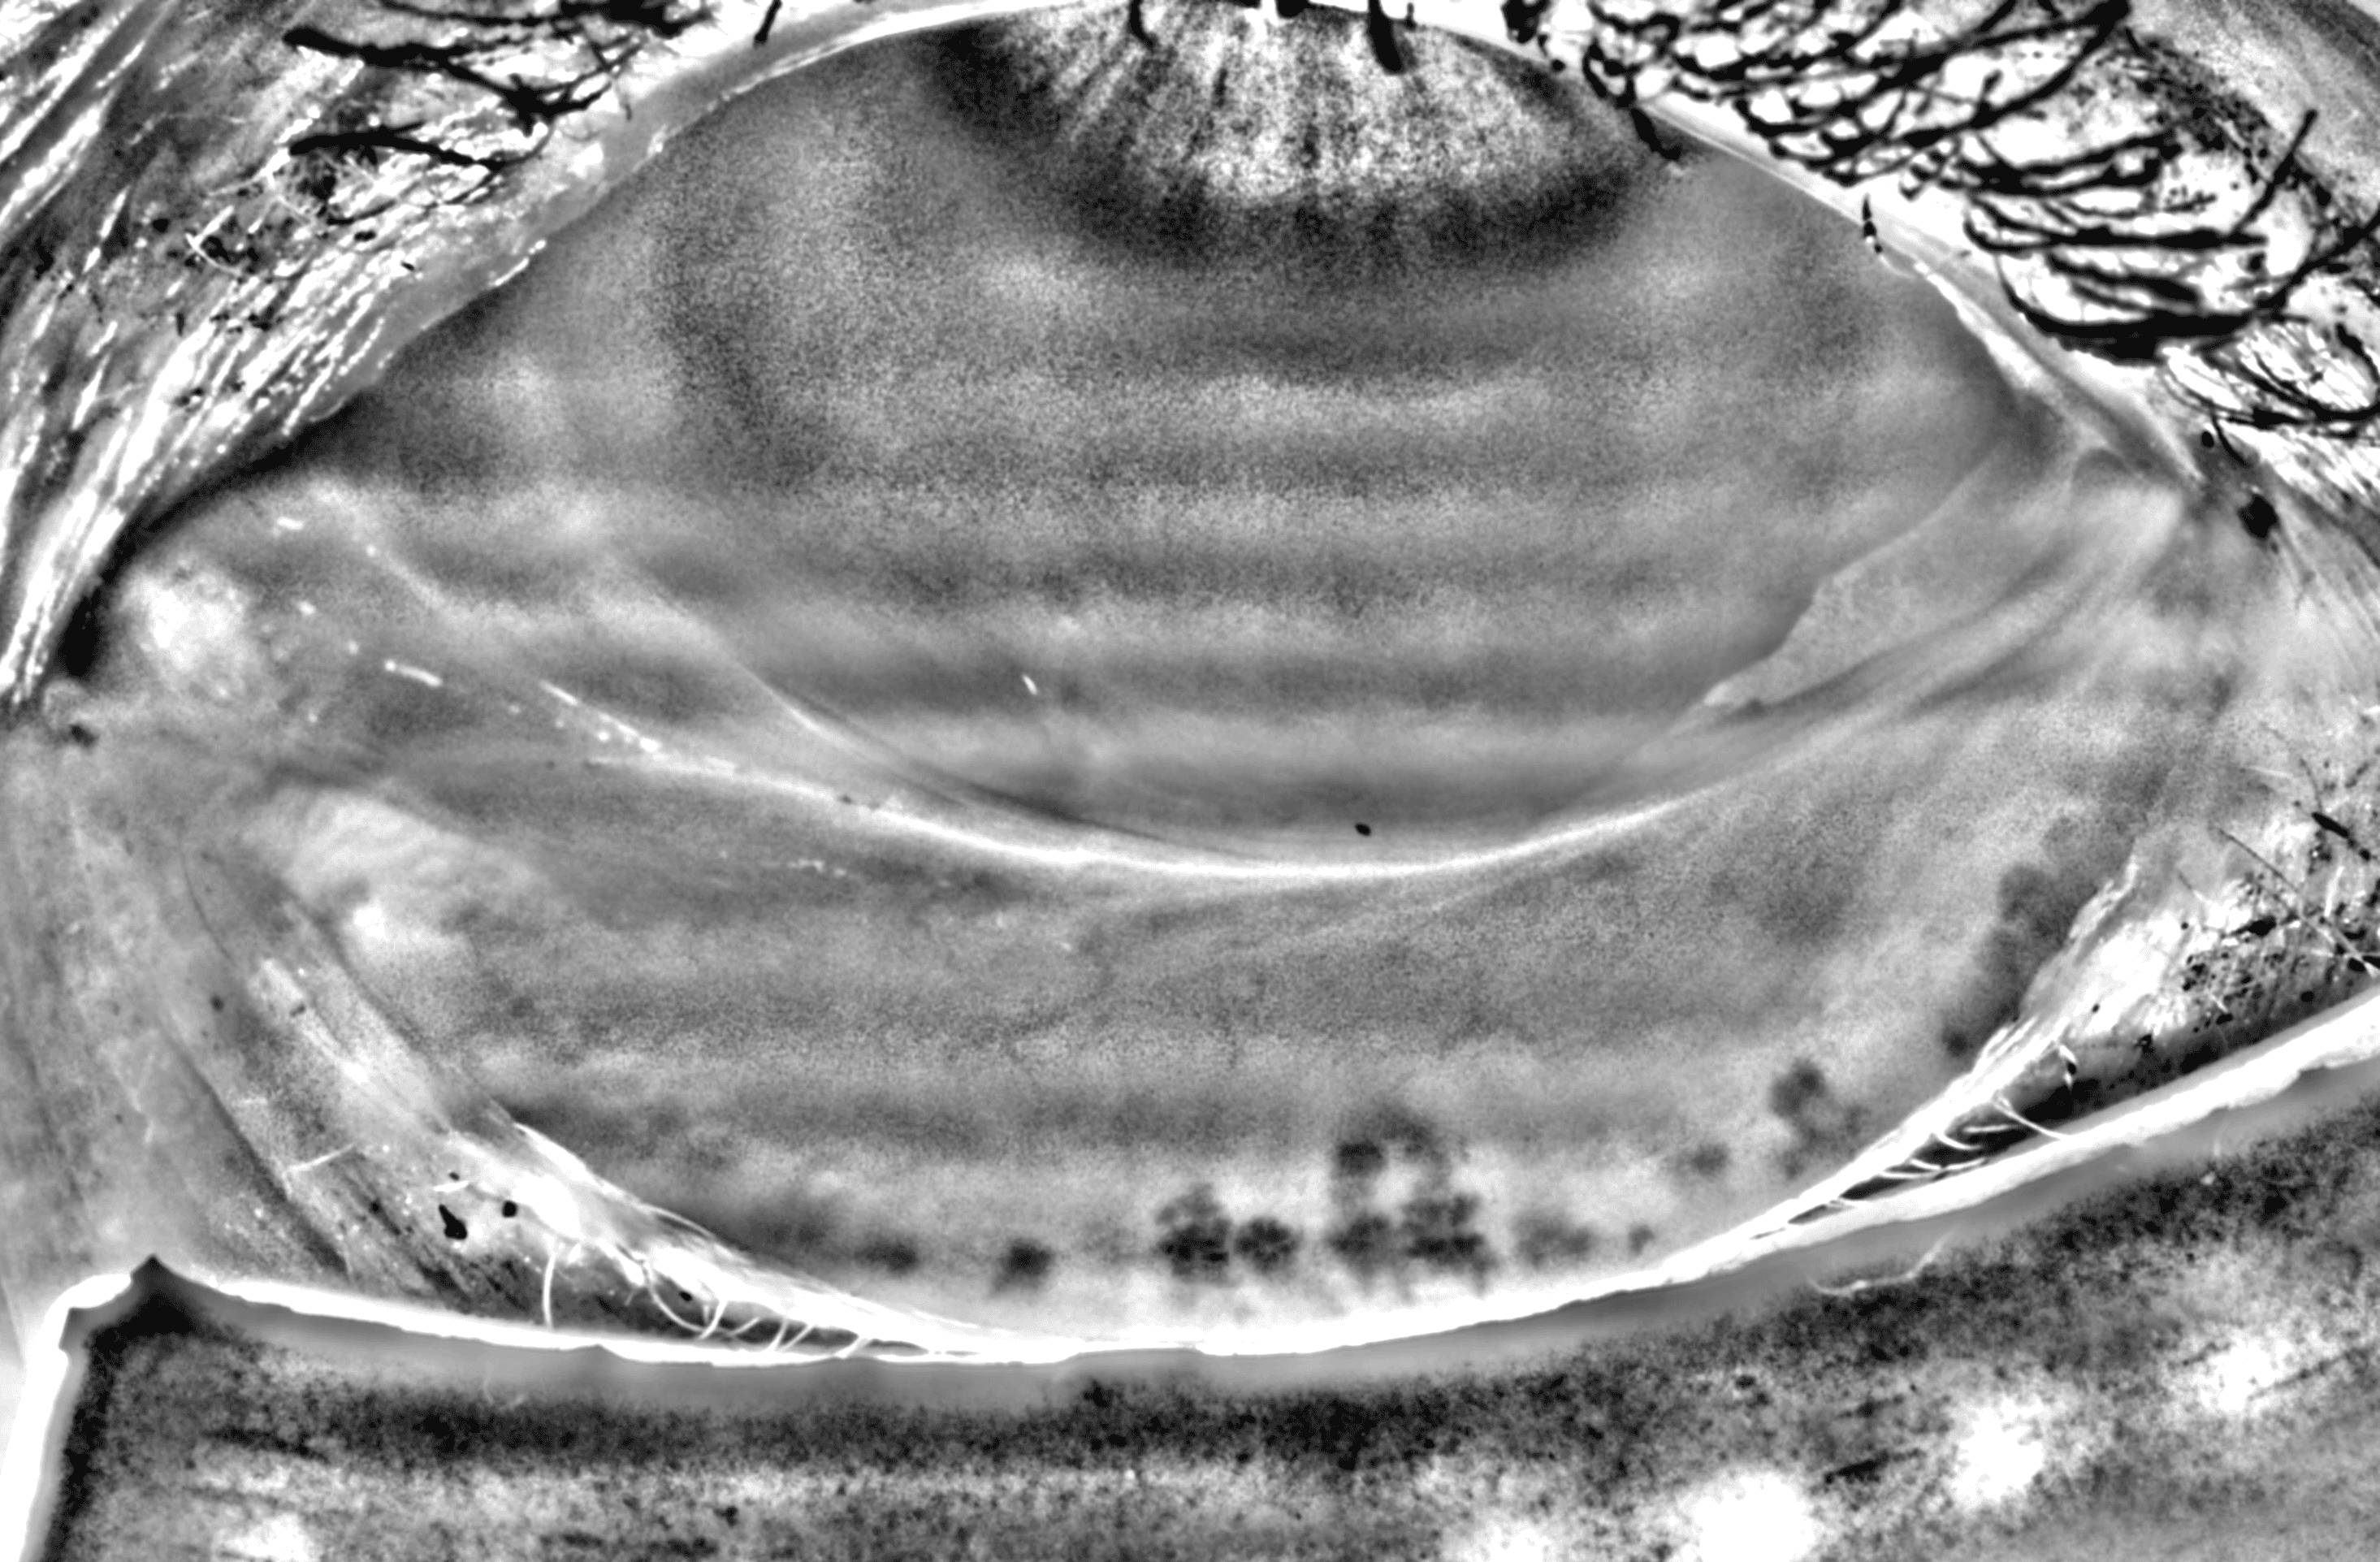

Capture and visualize meibomian gland structure, blink dynamics, tear film appearance, fluorescein imaging, and patient-reported symptoms using a single, compact device designed to integrate seamlessly into existing clinical setups.

See More with AI-Assisted

Real-Time Visualization

AI-assisted image processing enhances the visibility of ocular surface features, reducing time required manual image adjustments and allowing clinicians to focus on efficient clinical review. Operating directly on the live video stream, it provides immediate visual feedback that supports faster alignment, more confident image capture, and a smoother workflow.